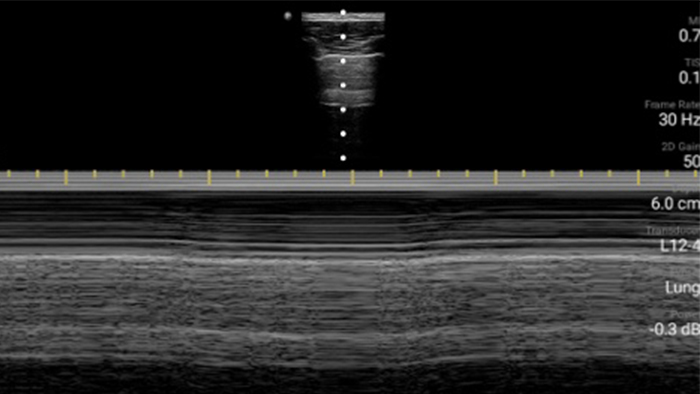

System Lumify to doskonałe rozwiązanie do badań górnych i dolnych dróg oddechowych

System Lumify do badań POCUS może służyć do wykrywania rurki dotchawiczej w tchawicy, pomagać podczas pilnych zabiegów konikotomii, diagnostyce wysięku opłucnowego oraz chorób pęcherzyków płucnych.